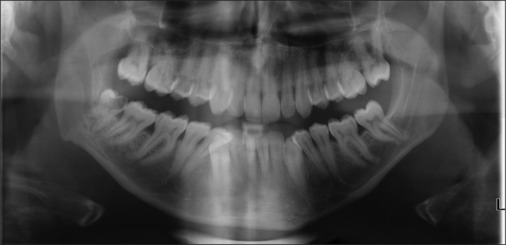

Objectives: The aim of this work is to evaluate the possibility that the three-dimensional (3D) reconstruction of a cone beam computed tomography (CBCT) scan may facilitate the technical planning of the surgical extraction of third molars, whose roots are located in proximity of or in contact with the inferior alveolar nerve.

Materials and methods: This article describes the planning process and the extraction of a lower third molar with the inferior alveolar nerve (IAN) entrapped through its roots using the 3D reconstruction of a CBCT scan.